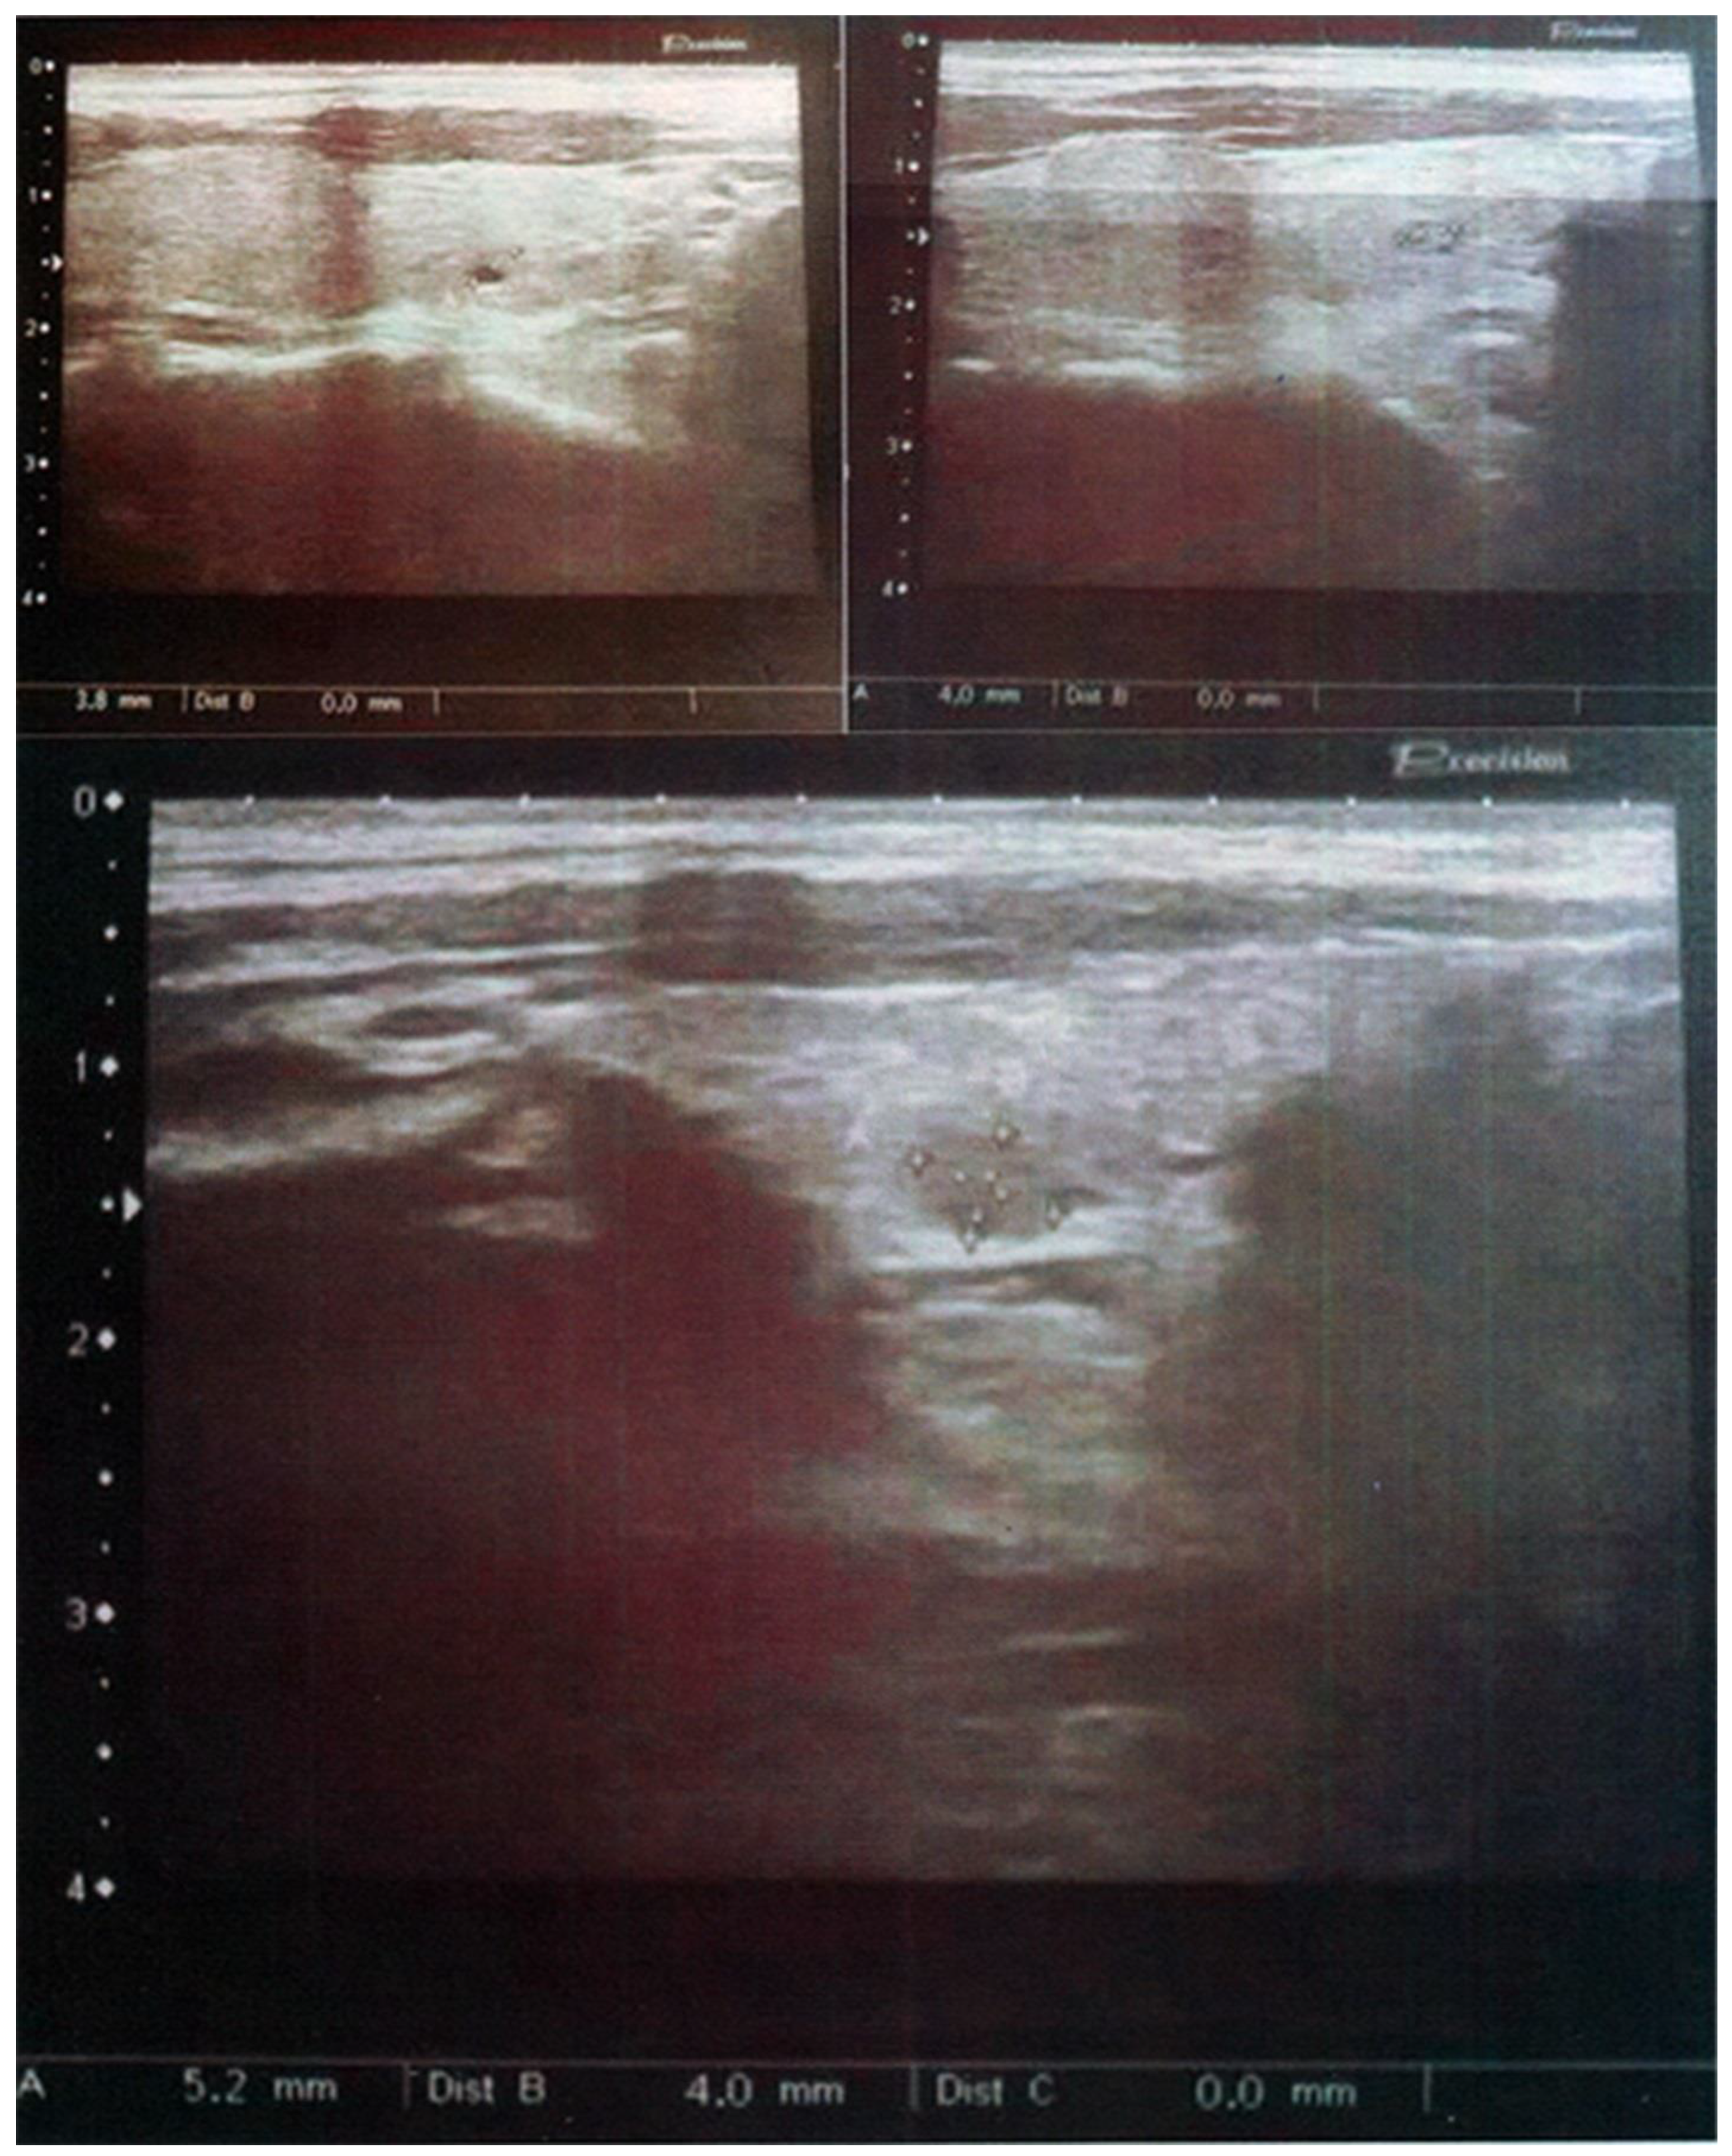

2.1. Case 1

2.2. Case 2